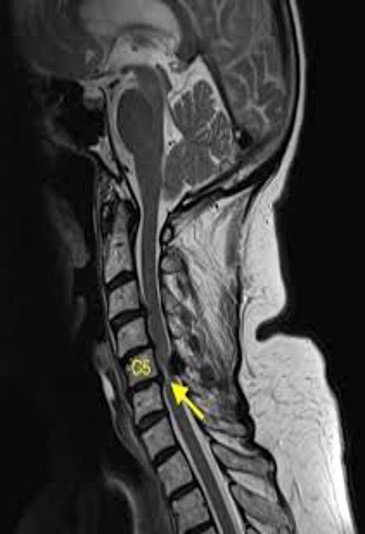

At the C5/6 intervertebral level (arrows, a and b), mild T2 hyperintensities around the anterior horns were observed on the axial plane.

(c) The hyperintensities became a pair of apparent hyperintense lesions on DWI.

(d) Image corresponding to owl’s eyes sign. The lesions on the axial DWI were hypointense on ADC maps .

(e). She was diagnosed with spinal cord infarction. ADC, apparent diffusion coefficient; DWI, diffusion-weighted imaging; MRI, magnetic resonance imaging.